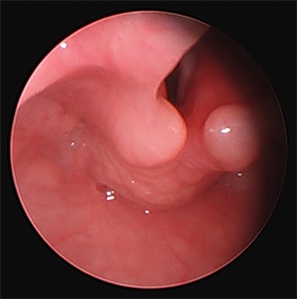

Intraoperative: Upon arrival to the operating room, standard ASA monitors were applied, the patient was induced with 8% Sevoflurane and a 22-gauge intravenous line (IV) was placed. A propofol infusion was started at initial rate of 500 mcg/kg/min and he was placed on nasal cannula at 4 L/min (equivalent to 20 L/min in a 75 kg adult). Glycopyrrolate (0.008 mcg/kg) and Tylenol (15 mg/kg) were given immediately after the IV was place. We avoided the use narcotic and benzodiazepines (No premedication). We monitored the ETCO2 via the nasal cannula as we titrated the anesthetic to a level needed for these procedures. When the ETCO2 decreased from baseline, we would decrease the infusion by 50 mcg/kg/min down to 400 mcg/kg/min. When the pattern and the ETCO2 increased from baseline, we would increase the infusion by 50 mcg/kg/min until 800 mcg/kg/min, but we have used up to 1000 mcg/kg/min. If the patient responds, we increase the infusion. The Otolaryngologist does a “test” laryngoscopy and anesthetized the vocal cords and surrounding tissue with topical 2% lidocaine. In this case, we had excellent conditions with 800 mcg/kg/min. Without the presence of the endotracheal tube, the surgical team had a full unobstructed view of the surgical site (Figure 1). And, since the patient was spontaneously breathing they were able to observe the airway dynamics. If the patient became apneic, we

Figure 1. Direct rigid laryngoscopy was performed. Then redundant tissue around the arytenoids is easily seen.